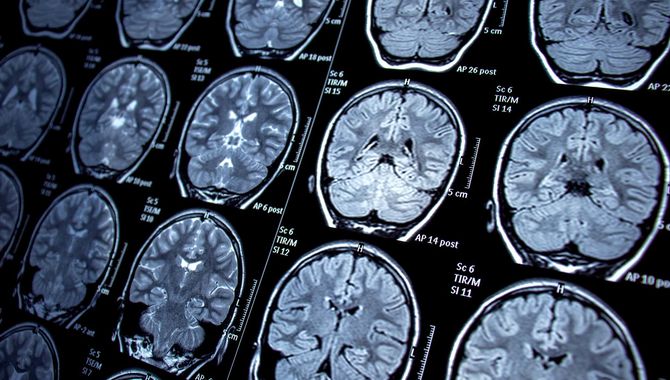

Spotlights Posts for Spotlights Predicting Aphasia Recovery An interdisciplinary study uses machine learning to determine how well stroke survivors with aphasia will respond to therapy The Healing Power of Music, from Bach to Rock Lou Awad is harnessing the power of music and rhythm to teach stroke survivors to walk again Bridging the Cognitive Therapy Gap Magdalen Balz’s CogWell program provides mental acuity resources for seniors historically neglected by the medical field Communication, Community, and Healthcare Hagere Yilma is working to reduce iron-deficiency anemia in rural India as lead researcher for the RANI Project. A Place to Practice Sargent’s new Center for Clinical Simulation will prepare students for real-world patient interactions Steering the Ship Sargent trains some of the world’s top physical therapists. Leading and encouraging them is clinician, researcher, professor, and department chair Terry Ellis Autism, from Every Angle Sargent researchers are helping us better understand one of the most complex brain mysteries of our time New Center for Brain Recovery Aims to Advance Treatments for Stroke, Alzheimer’s, Parkinson’s Interdisciplinary research hub brings together diverse experts to improve understanding of the brain and test new ways of restoring function. Sargent College Dean Christopher Moore Will Retire at the End of the Academic Year Credited with raising the college’s national profile, he plans to return to the Pacific Northwest. Graduate Programs Open House | Thursday, September, 8 Join us to learn more about graduate programs in OT, PT, SLHS, Human Physiology, and Nutrition. Jana Iverson, Renowned Movement and Communication Development Researcher Joins Department of Physical Therapy Iverson is an internationally recognized scholar in child development, studying early motor development and language skills. The Line Between Biology and Technology Has Blurred—There’s No Going Back BU scientists including Basilis Zikopoulos reflect on how this interface has changed the world. Functional Near-Infrared Spectroscopy Reveals Brain Activity on the Move Professors Simone Gill and Swathi Kiran are using fNIRS to explore brain activity in populations and places once considered inaccessible. Professor Jennifer Zuk Receives Inaugural Dyslexia Foundation Research Award Zuk and her research team will study factors associated with early risk for dyslexia among preschool-aged children. Reducing Barriers to Anemia Treatment Professor Hagere Yilma helped build a transformative public health intervention to boost health and iron levels for women in India. Spotlights navigation ← Previous Next →